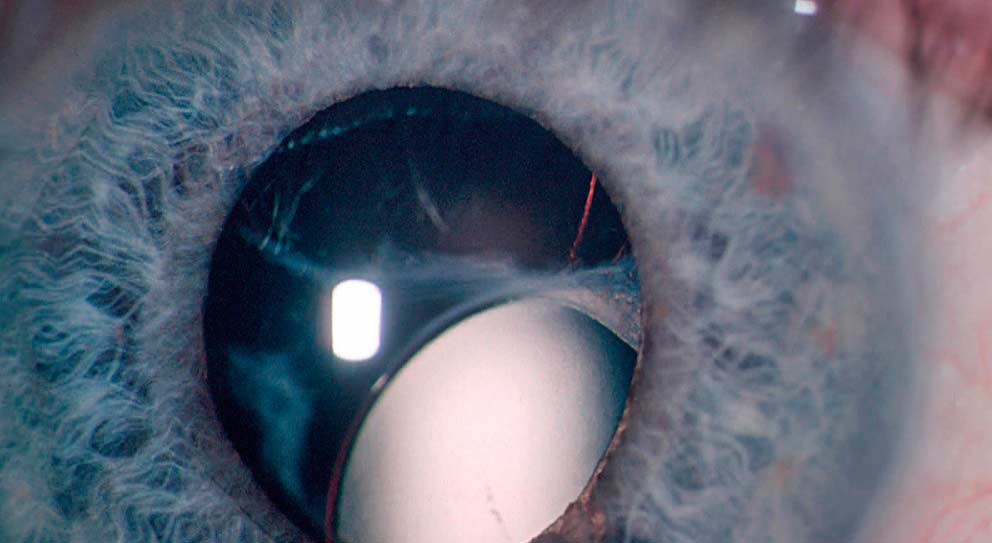

Катаракта представляет собой помутнение хрусталика, в результате чего он теряет свою прозрачность. Эта болезнь развивается из-за накопления нерастворимых белковых фракций, которые оседают внутри хрусталика, в итоге он становится белым, а затем желтеет.

| Вывих хрусталика | Полное смещение хрусталика из его нормального положения в стекловидное тело или переднюю камеру глаза. | Резкое снижение зрения, боль, покраснение глаза, двоение, иридодонез. |

При данной патологии хрусталик может смещаться как частично, так и полностью, что влияет на степень нарушения рефракции. Если линза остается в пределах зрачка, то изменения в оптической силе могут быть минимальными.